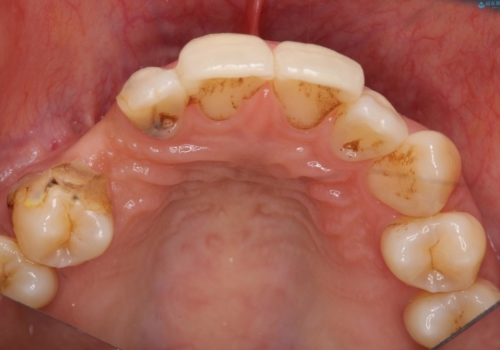

- 右上の歯はもともとなかったが、ブリッジにするのが嫌でプラスチックの歯を応急的に接着剤でつけていたのがとれてしまったとのことでした。

接着剤で留めてある周りが、虫歯になってしまっていました。

しっかり虫歯を取ったうえで、清掃性の高いブリッジにしていくことをおすすめしました。

右上④3②①ブリッジの設計としました。